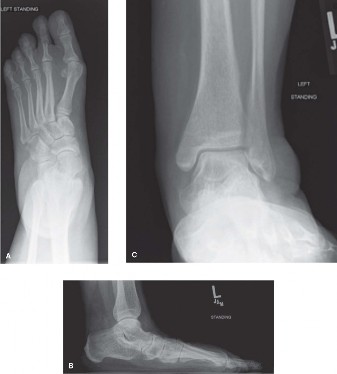

A 52-year-old female presents to you reporting left foot pain that has been present for the past 3 months. Sh…

A 50-year-old male presents with 6 months of atraumatic forefoot pain. He has noticed the gradual onset of pa…

A 54-year-old woman presents to clinic reporting discomfort on the dorsum of her foot with shoewear and pain …